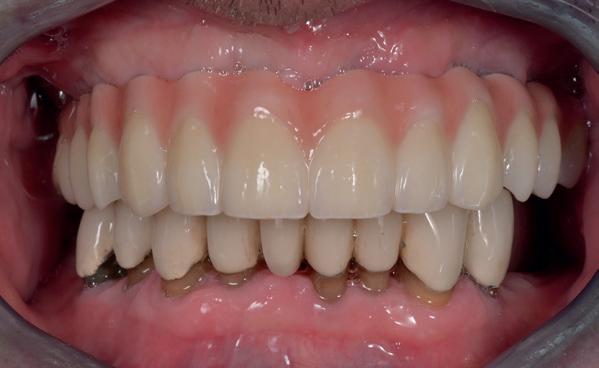

patiënt kon 2 maanden functioneren met de tijdelijke brug, waarna een kort consult werd gepland om te bespreken of hij tevreden was met de esthetiek en functie. Voor de patiënt hoefde niks veranderd te worden (afbeelding 11-14).

13. Na plaatsen tijdelijke brug op de implantaten

14. Portretfoto met tijdelijke brug

20. Frontaanzicht brug

Daarna werden de schroefgaten gevuld met Blue M gel, teflon tape en composiet (afbeelding 19 en 20). Patiënt was zich zeer tevreden met het functionele en esthetische eindresultaat (afbeelding 19 en 20). Er was ook een nette hoektand en frontgeleiding. Voor de fonetiek werd een filmpje opgenomen, de F en de S werden netjes uitgesproken (afbeelding 21). De patiënt vervolgt zijn parodontale nazorg bij de mond-

hygiënist waarbij ook de mondhygiëne bij de brug wordt gecontroleerd. Op de OPT na 2 jaar (afbeelding 22) is het botniveau rondom de implantaten stabiel en is patiënt tevreden met zijn vaste brug.